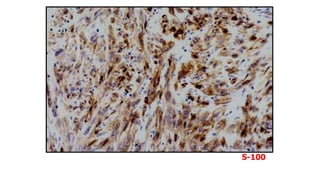

Thoracoscopic lung biopsy

S100

CD1a

FINAL DIAGNOSIS

• Pulmonary LCH